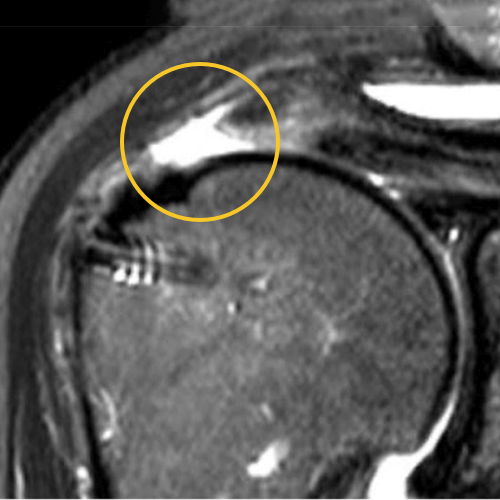

This is one of my cases, a 55-year-old woman, when her primary rotator cuff repair was done, we used Dermis on Demand, which is an allograft skin that can be utilized to help strengthen repairs. At four months out, the patient presented with pain and weakness following a traumatic injury and wound up re-tearing.

You can see a clear retear to the rotator cuff here with slight retraction, and some degeneration and thickness to the tendon.

We published this case study in the JOEI (Journal of Orthopedic Experience and Innovation) Journal. We did a revision of the large type-II repair and augmented it with BioBrace®. You can see the pre-op and three-month MRI below. Still fluid in the subacromial space but that tendon is clearly coming across into the footprint. Then, an eight-month MRI shows there's no further fluid in the subacromial space and maturation of that repair across the footprint.